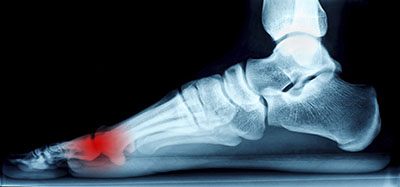

A podiatrist can diagnose Morton’s neuroma by taking a medical history and completing a physical examination. Sometimes imaging studies are used to confirm the diagnosis. Treatment is typically conservative and may include padding the foot, wearing orthotics, modifying footwear and activities, resting and icing the affected foot, taking anti-inflammatory medications, or injecting medicine directly into the foot. In severe or chronic cases, surgery may be recommended.